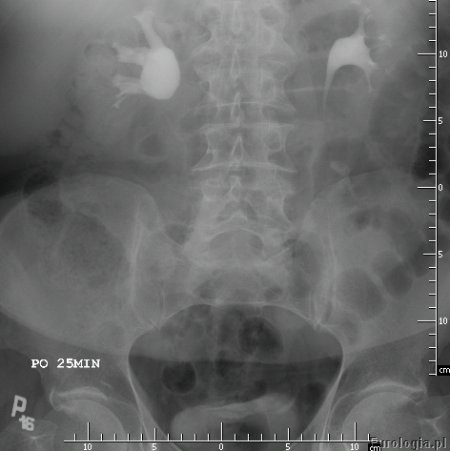

Fot. Urograficzny obraz zwężenia miedniczkowo-moczowodowego po stronie prawej.

Urografia jest badaniem czynnościowo - morfologicznym pozwalającym na ocenę budowy i funkcji układu moczowego. Badanie polega na dożylnym podaniu środka kontrastującego i wykonaniu serii zdjęć rentgenowskich. Środek kontrastujący wydzielany jest do moczu co widoczne jest na zdjęciu jako zakontrastowanie układu kielichowo - miedniczkowego i moczowodu.